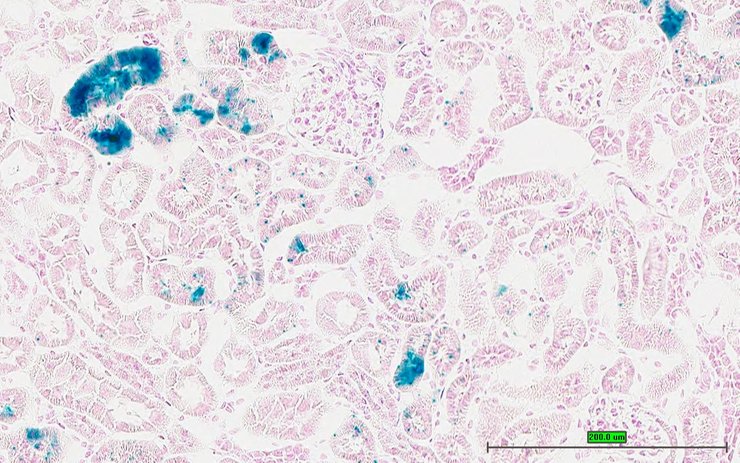

TS28: metanephros Present UC Davis_1883626 kidney

TS28: metanephros Present UC Davis_1883627 kidney

TS28: metanephros Present UC Davis_1883628 kidney

TS28: metanephros Present UC Davis_1883615 kidney

TS28: metanephros Present UC Davis_1883616 kidney